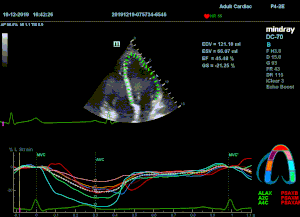

Всё изменилось с появлением технологии Speckle-tracking. Ультразвуковые приборы компании Mindray DC 8, 70, 80, Resona 6,7 оснащены данной функцией. Для использования необходим ЭКГ-канал. В чем же смысл данного технологического новшества? Прибор использует видео петли сечений миокарда, разбивает миокард на точки со стабильной визуализацией – speckle, и затем производит слежение каждой точки в течении нескольких сердечных циклов. Изменение пространства между точками дает нам представление о возможностях деформации миокарда, как продольной – Longitudinal Strain, так и деформации скручивания – торсии и Radial Strain.

Как работать с данным методом? Для Longitudinal Strain необходимо записать видео петли апикальных сечений в память прибора: 4С, 3С, 2С. Для повышения качества трекинга рекомендуется производить запись на выдохе пациента. Затем произвести разметку по линии эпикарда, перикарда и центра миокарда. Нажатием кнопки «начать слежение» активируется программный алгоритм, видео петля оживает вместе с размеченными точками-speckle’ами. При необходимости производится коррекция. После анализа всех трех сечений можно получить данных продольной деформации как в среднем значении, так и по каждому сегменту миокарда левого желудочка. Нормальным показателем считается Longitudinal Strain -20%. Нижней границей -14%.

Видео примеры на приборе Mindray DC 70